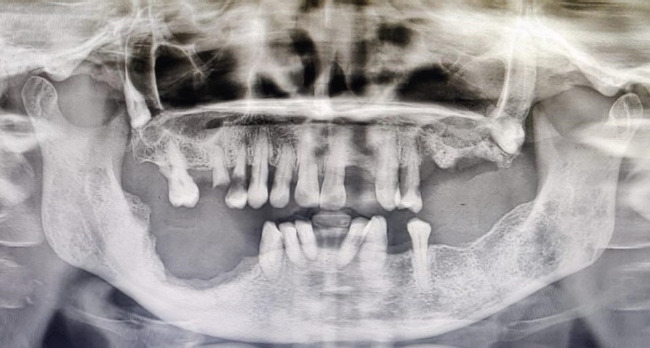

药物相关性颌骨骨坏死(MRONJ)是一种相对罕见但文献充分的双膦酸盐治疗并发症。双膦酸盐被开给数百万的骨质疏松症、佩吉特病、多发性骨髓瘤、骨转移和其他骨相关疾病的患者。这些药物通过与羟基磷灰石结合来抑制骨吸收,特别是在主动吸收区域,从而阻止破骨细胞附着在骨上。长期双膦酸盐治疗被认为是MRONJ的主要危险因素。双膦酸盐引起的骨坏死通常表现为牙槽骨外露,可能自发发生,也可能在有创性牙科手术(如拔牙、根尖切除术或植入物)后发生。本病例报告描述了一名女性,在接受双膦酸盐治疗多发性骨髓瘤和随后的拔牙后,在上颌骨和下颌骨发生骨坏死。

Medication-related osteonecrosis of the jaw (MRONJ) is a relatively rare but well-documented complication of bisphosphonate therapy. Bisphosphonates are prescribed to millions of patients for the treatment of osteoporosis, Paget's disease, multiple myeloma, bone metastases, and other bone-related conditions. These drugs inhibit bone resorption by binding to hydroxyapatite, particularly in areas of active resorption, thereby preventing osteoclasts from attaching to the bone. Long-term bisphosphonate therapy is considered a primary risk factor for MRONJ. Bisphosphonate-induced osteonecrosis typically manifests as exposed alveolar bone, which may occur spontaneously or following invasive dental procedures such as extractions, apicectomies, or implant placement. This case report describes a female who developed osteonecrosis in the maxilla and mandible after undergoing bisphosphonate therapy for multiple myeloma and subsequent tooth extractions.